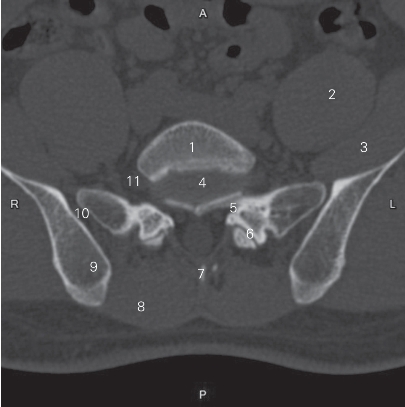

图3-3 经第5腰椎椎体的横断层CT图像(骨窗)

1 第5腰椎椎体 5th lumbar vertebral body 2 腰大肌 psoas major

3 髂肌 iliacus

4 第5腰椎间盘 5th lumbar intervertebral disc 5 侧隐窝 lateral recess

6 关节突关节 zygapophysial joint 7 棘突 spinous process

8 多裂肌 multifidi 9 髂骨 ilium

10 骶髂关节 sacroiliac joint

11 第5腰神经 5th lumbar nerve